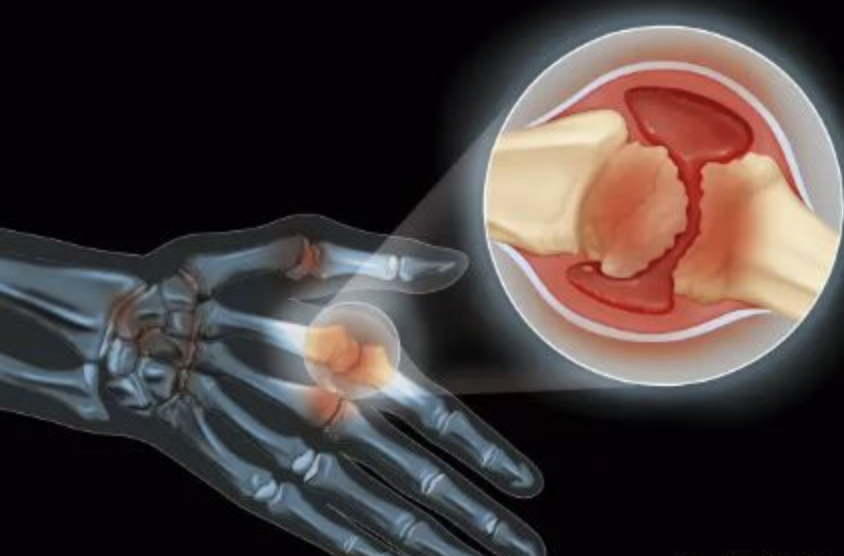

无临床症状高尿酸血症可以吃非布司他吗

*ST龙津:非布司他片获得药品补充申请批准通知书公司近日收到国家药品监督管理局核准签发的《药品补充申请批准通知书》,批准非布司他片上市许可持有人由“芜湖杨燕制药有限公司”变更为“昆明龙津药业股份有限公司”,药品批准文号不变。非布司他片适用于痛风患者高尿酸血症的长期治疗,不推荐用于无临床症状的高尿酸血症...

华润双鹤:非布司他片获得药品补充申请批准通知书金融界11月5日消息,近日,华润双鹤收到国家药监局颁发的非布司他片《药品补充申请批准通知书》。该药品适用于痛风患者高尿酸血症的长期治疗,不推荐用于无临床症状的高尿酸血症。公司于2023年6月14日获批40mg规格上市,为满足不同患者需求,2022年3月启动增加20mg规格的补...

⊙^⊙ 中关村(000931.SZ):非布司他片药品注册申请获受理中关村(000931.SZ)公告,公司下属公司多多药业有限公司(简称:多多药业)于近日收到国家药品监督管理局签发的《受理通知书》,非布司他片(规格:20mg、40mg)药品注册申请获得受理。本次申报产品适应症为适用于痛风患者高尿酸血症的长期治疗,不推荐用于无临床症状的高尿酸血症...

中关村:下属公司非布司他片药品注册申请获受理南方财经11月12日电,中关村晚间公告,公司下属公司多多药业有限公司近日收到国家药监局签发的《受理通知书》,非布司他片(规格:20mg、40mg)药品注册申请获得受理。此次申报产品适应症为适用于痛风患者高尿酸血症的长期治疗,不推荐用于无临床症状的高尿酸血症。